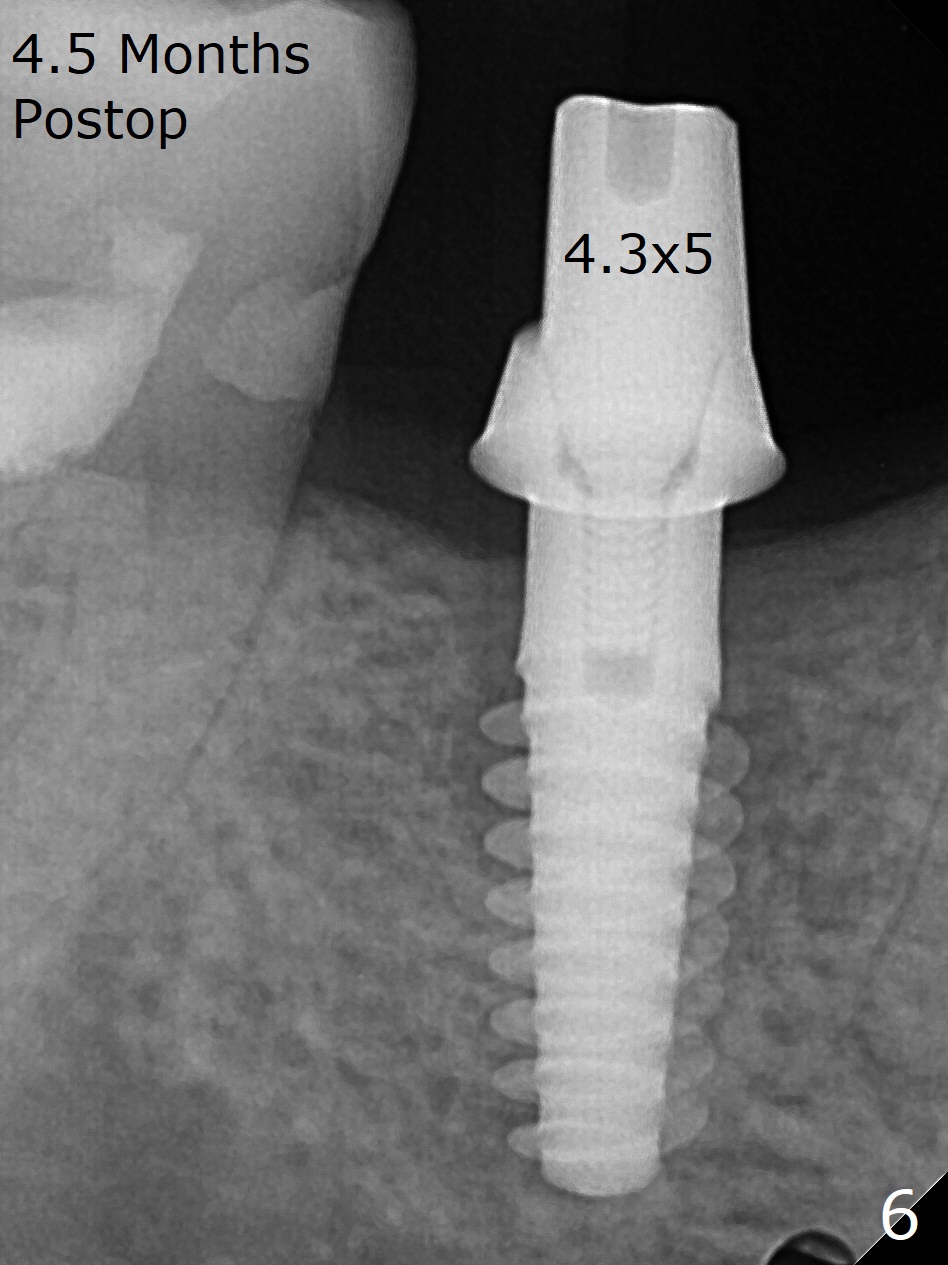

A 5x12 mm SM implant with periimplantitis at #30 is removed with a 5/6 mm trephine bur, small elevator and implant driver. A 3.8 mm Magic drill is used to start a new osteotomy in the lingual wall of the old one free hand. With the final drill (4.8x13 mm), a 5x11(3) mm Magicore is placed (Fig.1-4). The large buccal gap (Fig.2 arrowheads) is filled with allograft (Fig.3 *). The latter is covered by PRF, followed by suture. Periodontal dressing is applied around the 4.2x3 mm solid abutment and the coronal portion of the Magicore (Fig.4 <). The green outline in Fig.5 (CT coronal section) represents a new 5x10 mm implant (design), while the thick red line is approximately the long axis of the new implant. The implant heals in spite of buccal recession. Impression is taken with placement of a 4.3x5 mm solid abutment 4.5 months postop (Fig.6). Take follow-up CT to determine buccal bone formation.